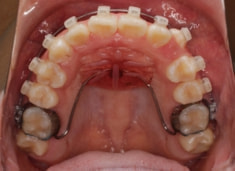

治療開始時

治療開始から5ヶ月後